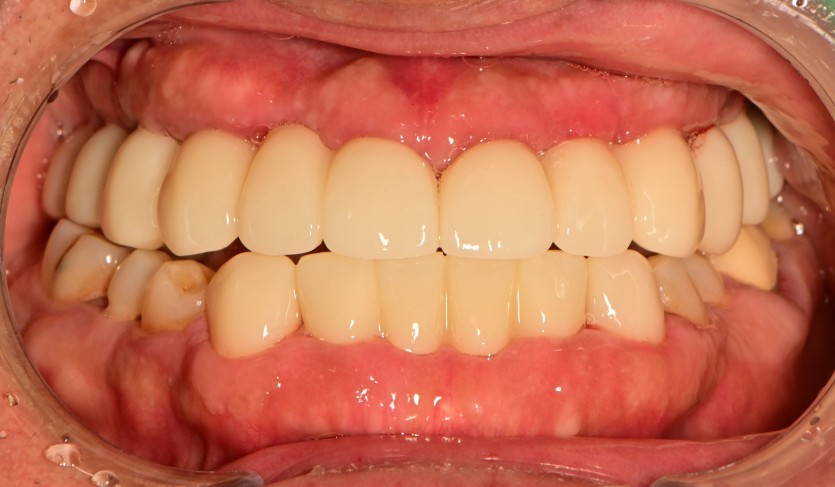

만 44세 상악 전체 임플란트 증례(하악 일부)

상악 전체 임플란트 증례입니다.(하악 일부)

13개의 임플란트로 완성하였습니다.